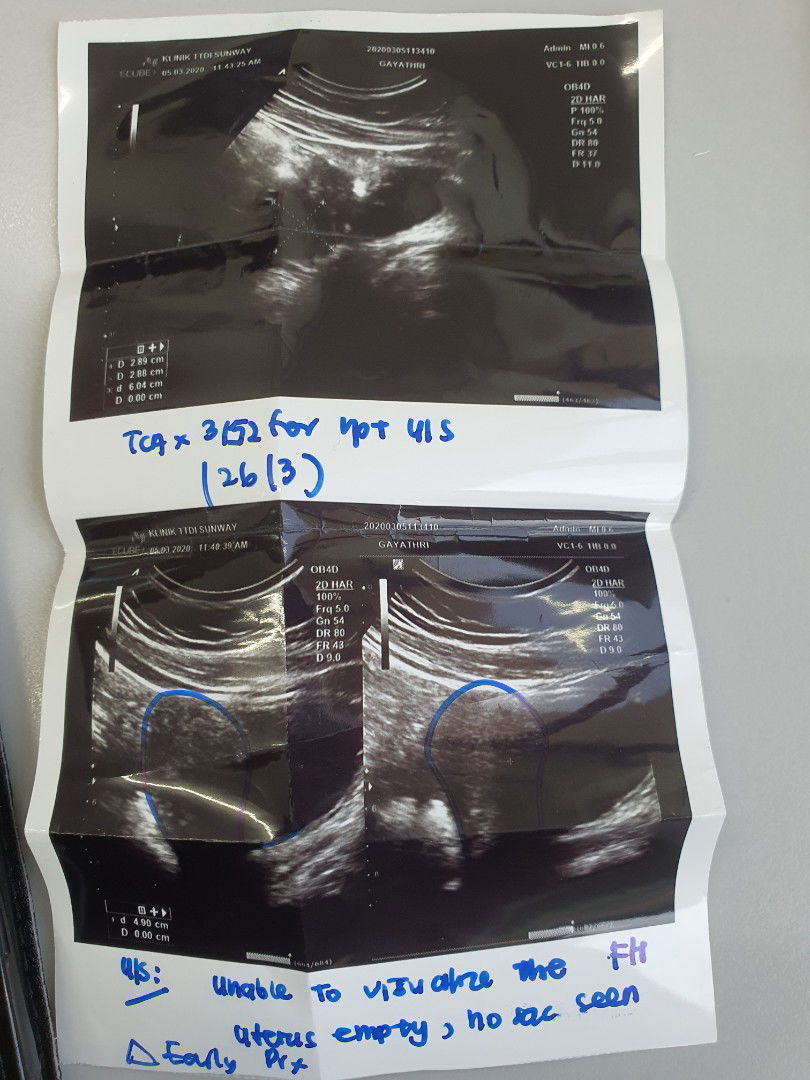

anyone experience light spotting and cramping during early pregnancy 4-6 weeks? normal ke? sy lewat period 15 Hari. upt negative. pegi scan ,doktor ckp early pregnancy. dlm 3 minggu kena scan lg sekali. By calculation 6 weeks. tapi dok scan Dan ckp baru mcm 4 weeks.